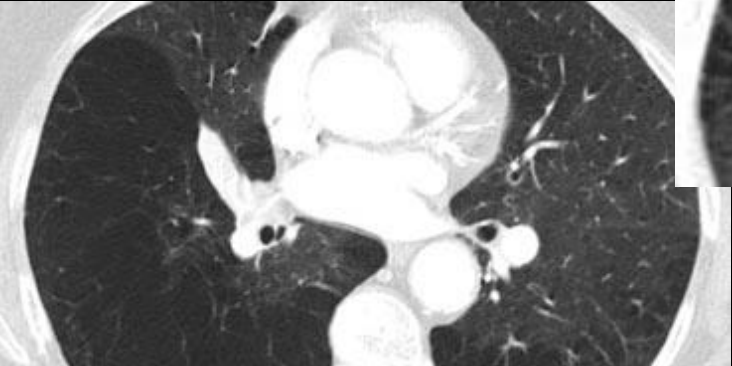

Que imagen distingue distribución en EPOC enfisematoso?

TC

Panlobulillar